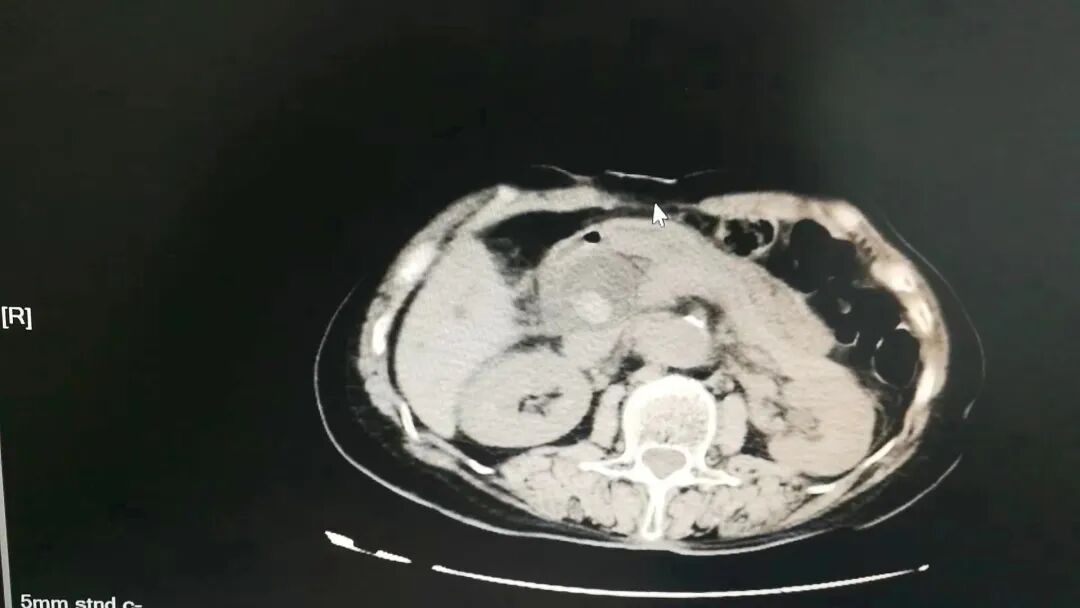

入院后予以抗感染、解痉止痛等对症治疗后,章阿姨病情无明显好转,仍然反复腹痛,疼痛剧烈时在床上直打滚!完善增强CT等相关检查后患者“胆总管多发结石并急性胆管炎,肝内外胆管扩张”诊断明确,手术指征明确。

▲CT影像